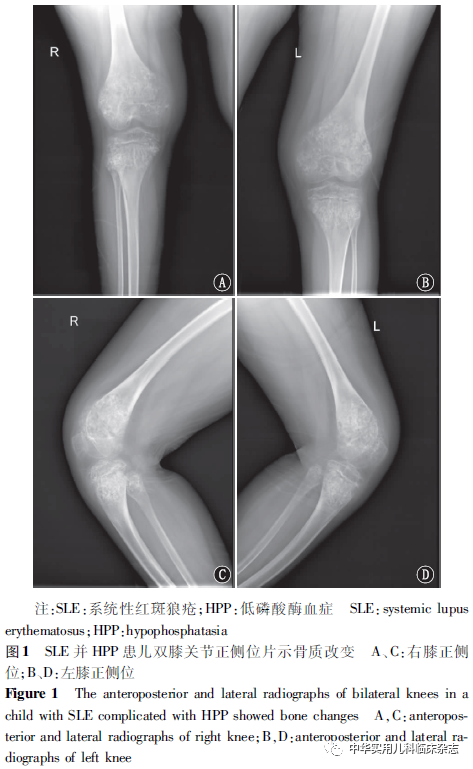

1

临床资料1.1 病史与体格检查 回顾性分析。患儿,男,10岁,因“发热伴颜面皮疹4 d”于2015年12月收治于吉林大学第二医院儿科。入院前4 d患儿无明显诱因出现发热,体温最高38.9 ℃,伴颜面皮疹,自行口服“头孢”3 d,仍有发热。病程中患儿出现单个手指肿痛,无光过敏。既往3岁时因口腔牙齿脱落、行走困难于吉林大学第二医院及北京某医院行肝/骨/肾型碱性磷酸酶(ALPL)基因检测确诊为HPP,无食物、药物过敏史,身高较同龄儿矮小,父母非近亲结婚,家族中无遗传病史及其他特殊记载。入院时体格检查:体温38.0 ℃,脉搏100次/min,呼吸25次/min,血压110/60 mmHg(1 mmHg=0.133 kPa),身高130 cm,体质量43 kg,一般状态可,行走缓慢似鸭步,面色略苍白,双侧面颊部皮肤可见多个米粒大小暗红色皮疹,不凸出皮面,压之不退色,口腔内侧可见2处溃疡,牙齿部分缺如,仅见8颗恒切牙及4颗恒磨牙。心肺腹及神经系统查体未见明显异常,四肢关节无红肿、无压痛。1.2 辅助检查 血常规示白细胞3.2×109/L、中性粒细胞1.00×109/L、淋巴细胞2.10×109/L、血红蛋白88 g/L、血小板98.0×109/L,尿常规示蛋白质(+),红细胞沉降率40 mm/1 h,肝功能示白蛋白37.8 g/L、ALP 17 U/L,肾功能示肌酐88.0 μmol/L、尿素氮13.59 mmol/L、尿酸455 μmol/L,血离子示钙 2.33 mmol/L、磷2.01 mmol/L,余项生化检查未见异常,便常规、C反应蛋白、降钙素原、血脂、空腹血糖未见异常。抗核抗体(ANA) 1∶1 000,抗双链(ds)-DNA抗体、抗心磷脂抗体、抗干燥综合征抗原A(SSA)抗体均阳性,核周型-抗中性粒细胞胞质抗体(p-ANCA)阳性,直接抗人球蛋白试验(IgG+C3)弱阳性,免疫球蛋白G 21.30 g/L、补体C3 108.0 mg/L、补体C4 17.8 mg/L。乙肝病毒等多种病原检测未见异常。双膝关节正侧位片(图1)示双侧股骨下端、胫骨及腓骨上端骨质呈膨胀性生长,密度减低,其内可见小囊状透光区,关节间隙尚可。胸部CT示两肺间质性炎症。心电图、肝胆胰脾肾及心脏彩超未见异常。1.3 诊疗经过及转归 入院后根据患儿临床表现及辅助检查,诊断为SLE并HPP,予甲泼尼龙60 mg/d、维生素D、钙剂治疗,加用头孢唑肟1.5 g/次,2次/d抗感染。此外,患儿全血细胞、网织红细胞减低,不除外骨髓造血异常,血液系统疾病确诊应依据骨髓穿刺,但患儿有HPP,骨髓穿刺风险较大,未予操作。入院第9天患儿尿中出现明显血尿及蛋白尿,尿常规示红细胞110.8/高倍镜(HPF)、蛋白质(+++),24 h尿蛋白定量1.19 g/24 h,补充临床诊断狼疮性肾炎,予加用免疫抑制剂吗替麦考酚酯0.25 g/次,3次/d口服。入院第15天患儿经激素及免疫抑制剂治疗后病情较平稳,出院继续口服上述药物治疗,定期随诊,于确诊SLE 2年后死于狼疮性肾炎和感染。本研究通过医院医学伦理委员会批准[批准文号:2021年研审第(154)号],患儿监护人知情同意。